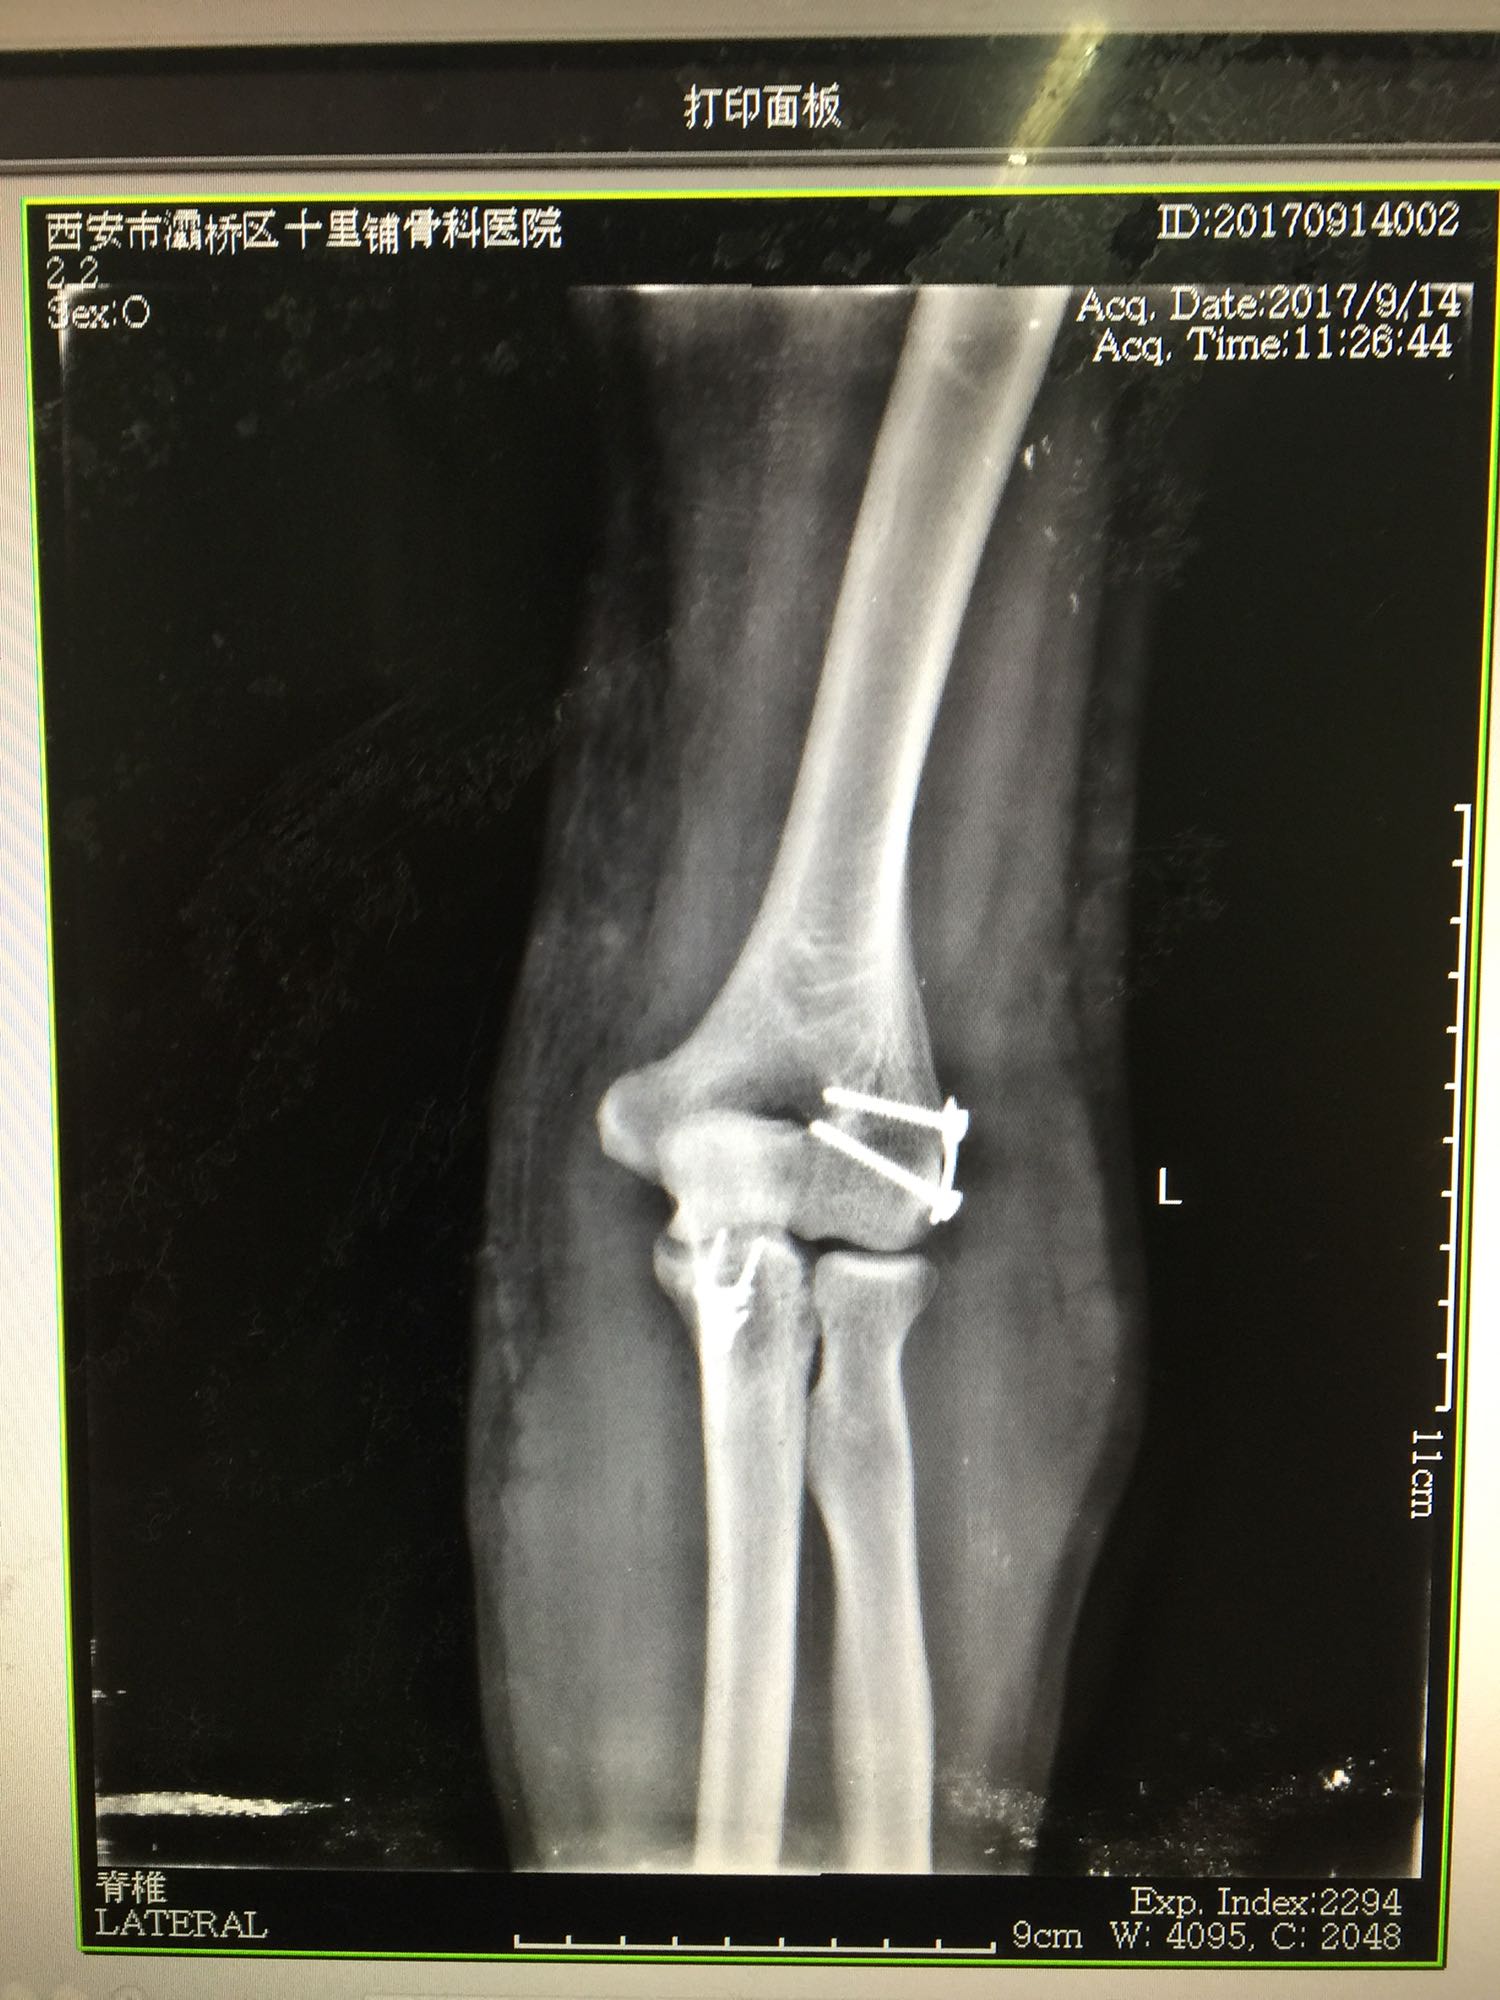

1、左尺骨冠状突骨折;2、左肱骨外髁撕脱骨折 治疗:入院后伤肢石膏外固定,给予局部冷敷消肿治疗,于伤后一周行骨折手术治疗,先行前内侧切口复位固定冠状突骨折,活动肘关节发现关节明显不稳定,随取外侧切口,复位固定肱骨外髁,修补外侧副韧带,肘关节明显稳定。术中术后片子如下

患者目前功能恢复满意,骨折愈合。